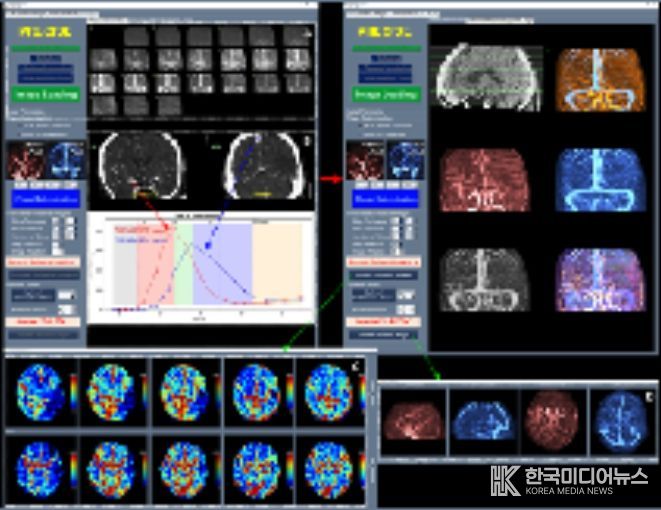

이와 함께 허혈성 뇌혈관 질환 환자를 대상으로 혈관재개통 치료가 필요한 환자 선별을 지원하는 소프트웨어 등 다양한 진단·치료 보조 AI 의료기기들이 혁신의료기기로 지정됐다.